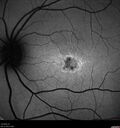

Fresh BRAO in patient with wet AMD72 views91 year old female She noticed last night a shadow over the left eye. When she closes her right eye she cannot see the bottom of the vision in the left eye. This is new.

VA OD: sc20/32-1

VA OS: sc20/32-2